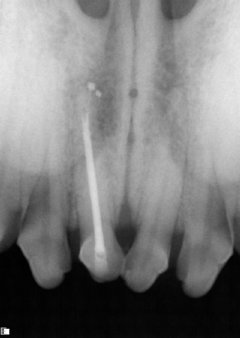

The incisor’s pulp chamber and root canal are filled with an inert material and a sealer cement to prevent future bacterial leakage into the canal space.